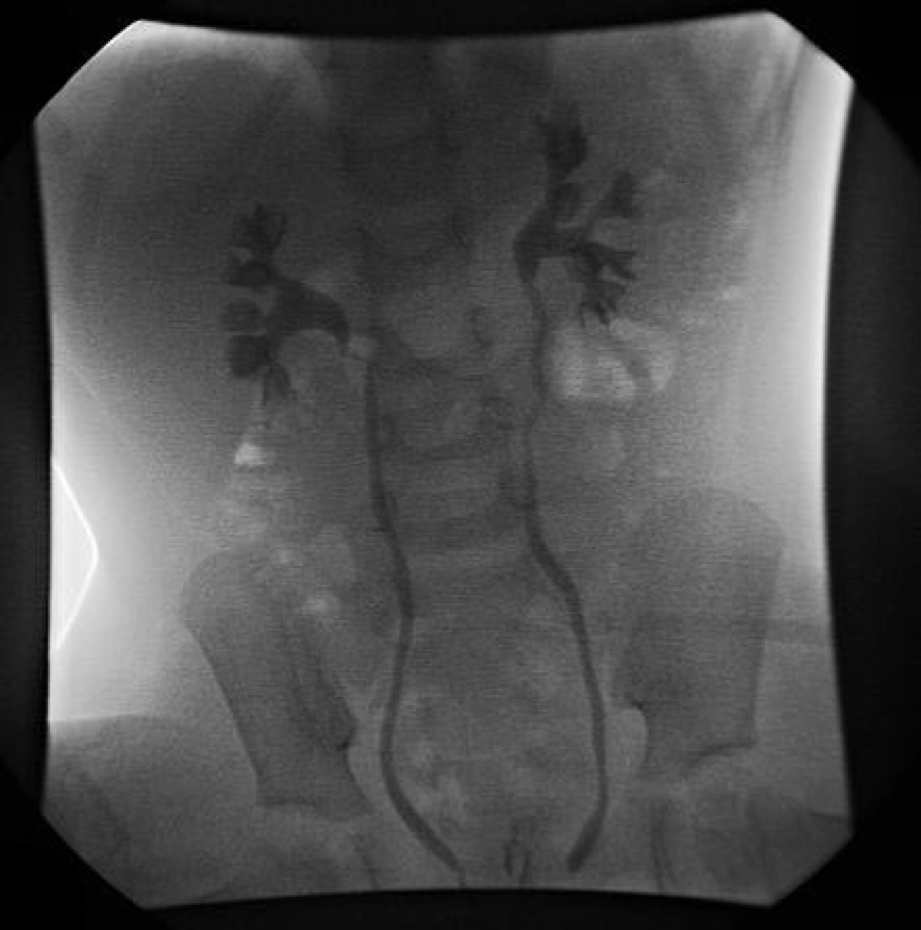

Is this fluoroscopic voiding cystourethrogram (VCUG) image of a 2 year old boy normal?

NO! this shows hydronephrosis indicating vesiculouretal reflux